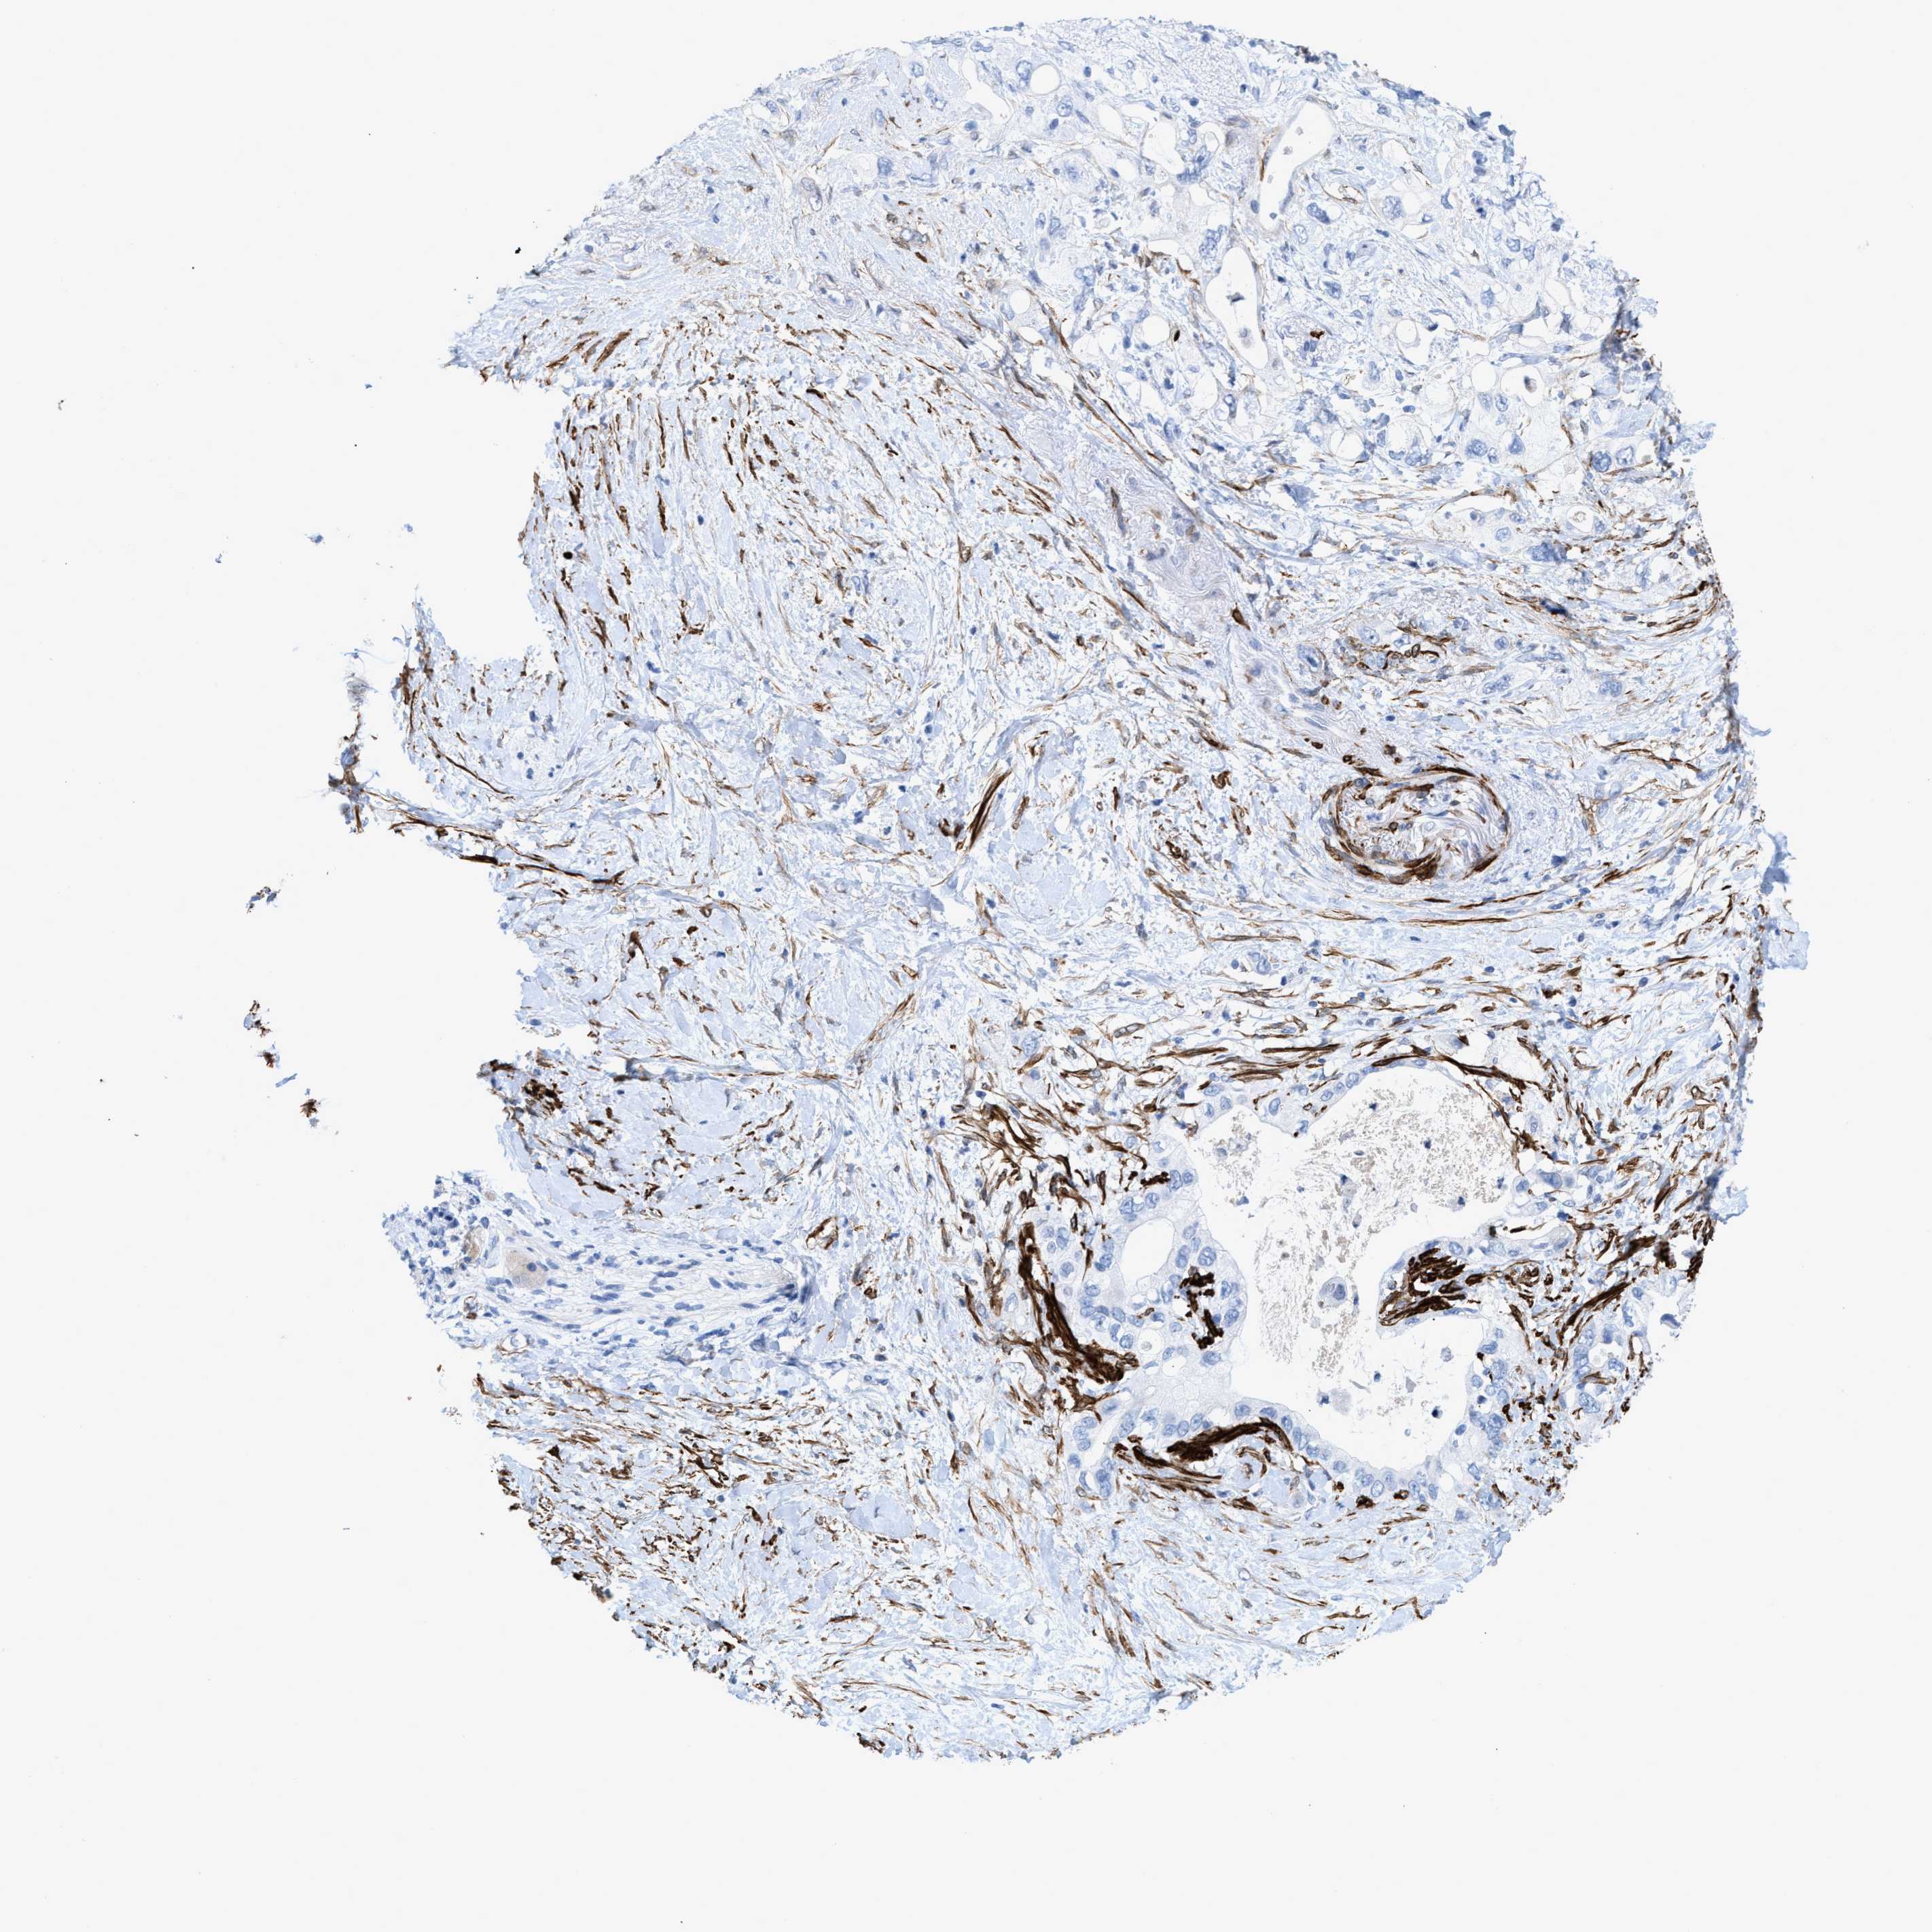

PANCREATIC CANCER - Protein expressioni

A mouse-over function shows sample information and annotation data. Click on an image to view it in a full screen mode. Samples can be filtered based on level of antibody staining by selecting one or several of the following categories: high, medium, low and not detected. The assay and annotation is described here.

Note that samples used for immunohistochemistry by the Human Protein Atlas do not correspond to samples in the TCGA dataset.

Antibody stainingi

Antibody staining in the annotated cell types in the current human tissue is reported as not detected, low, medium, or high, based on conventional immunohistochemistry profiling in selected tissues. This score is based on the combination of the staining intensity and fraction of stained cells.

Each image is clickable and will lead to virtual microscopy that enables deeper exploration of all samples and also displays staining intensity scores, fraction scores and subcellular localization as well as patient and tissue information for each sample.

Antibody HPA019467

Antibody HPA061657

Antibody CAB001447

Staining

High

Medium

Low

Not detected

Intensity

Strong

Moderate

Weak

Negative

Quantity

>75%

75%-25%

<25%

None

Location

Nuclear

Cytoplasmic/membranous

Cytoplasmic/membranous,nuclear

Adenocarcinoma, NOS